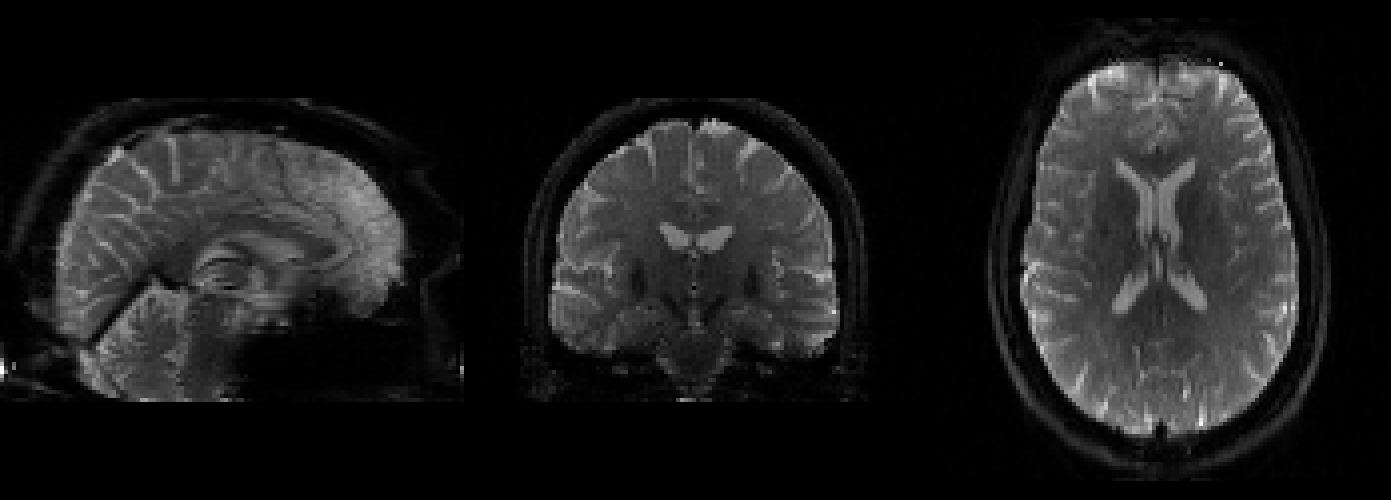

For example, fMRI data is affected by something known as susceptibility distortion, which causes the images that we read from the scanner to become warped.

This is due to the fact that our “3 Tesla” (3T) MRI scanner produces a magnetic field which is not exactly 3T, but in fact fluctuates by small amounts throughout the space inside the scanner. This distortion can be corrected by estimating the strength of the magnetic field, and then adjusting (a.k.a. unwarping) the images accordingly.

Another very common approach to correcting for this type of distortion is to acquire a field map, which is the scanner’s own estimate of its magnetic field, and to use that to unwarp our data.